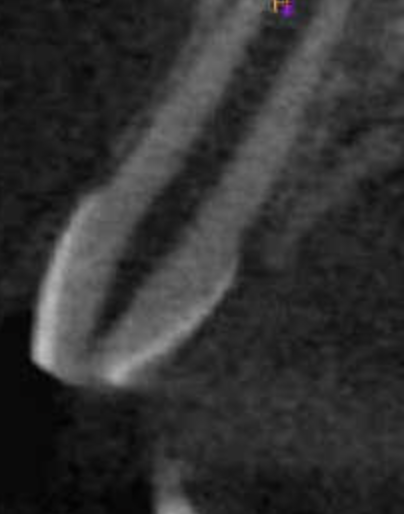

CALCIFICADOS

Premolar calcificado lesion